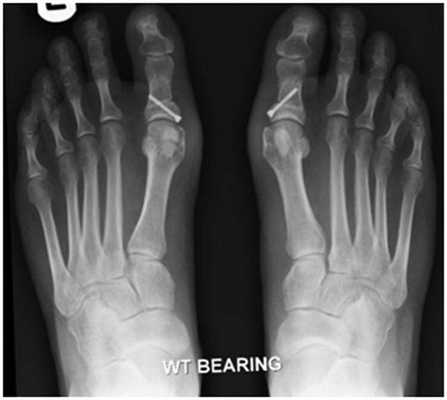

Клинический пример хирургического лечения hallux valgus 2 степени. Пациентка П. 32 лет, обратилась в клинику в связи с прогрессированием деформации 1 пальцев обеих стоп, усилением болей в области 1 плюсне-фаланговых суставов обеих стоп, трудностями с подбором обуви. Вальгусная деформация 1 пальцев или Hallux Valgus является наиболее частой причиной обращения за хирургической помощью к ортопедам, занимающимся проблемами стоп.

При клиническом осмотре обращает на себя внимание наружное отклонение 1 пальцев, расширенный и уплощённый поперечный свод стопы, нарушение плюсневой формулы, гиперкератозы по внутренней и тыльной поверхностям 1 плюсне-фаланговых суставов.

При планировании оперативного пособия выполняются рентгенограммы в прямой и боковой проекции. Производится расчёт углов вальгусного отклонения 1 пальца, угол между 1 и 2 плюсневыми костями, угол артикуляции 1 плюсневой кости. Исходя из рассчитанных углов, выбирается оптимальный метод остеотомии для коррекции имеющейся деформации.

Хирургическая тактика обсуждается с пациентом. Разъясняются особенности хирургического доступа, анестезиологического пособия, последующей реабилитации. Эту пациентку беспокоила деформация только 1 луча, вмешательства на 2-3-4-5 лучах стопы не потребовались.